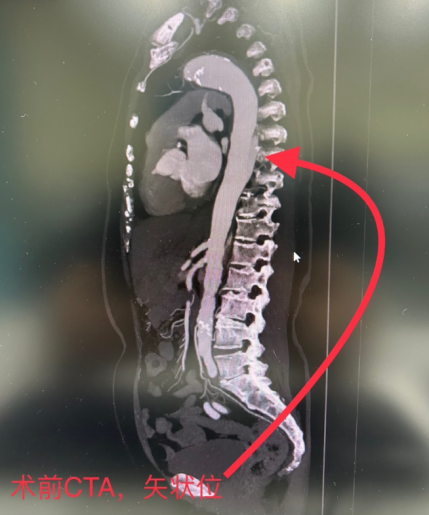

再说10月22日凌晨1点26分,患者王大娘被家人送到济南市中心医院东院区胸痛中心,进行CTA检查,提示:主动脉夹层Stanford B型。

CTA是什么?济南市中心医院东院血管外科主治医师温永冰介绍:CTA是CT血管造影的简称,大医院胸痛中心在救治胸痛症状患者时常规进行的一项检查,通过患者的上肢静脉快速注入碘对比剂,根据每一位患者的血液循环状态,在靶血管中对比剂浓度最佳的时刻进行CT扫描,其后通过计算机的后处理技术,重建出血管的三维影像。

*CTA结果帮助医生快速确诊病情

CT血管造影(CTA)目前被广泛用于血管性疾病的诊断,如动脉粥样硬化、动脉炎、血栓形成、动脉瘤、主动脉夹层等等。也可以通过对肿瘤供血动脉的影像评估,进行肿瘤的定位、定性诊断,提供治疗方案等等。